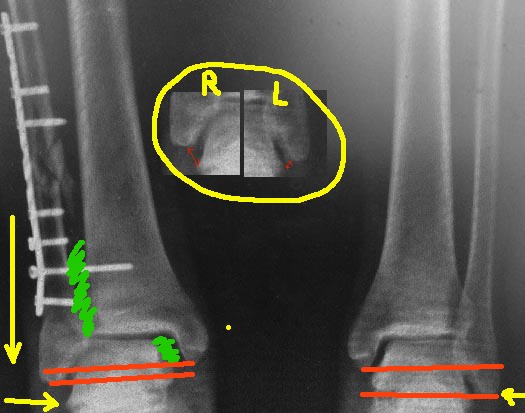

Я немного порисовал на вашем рентгенснимке, чтобы было понятно. теперь

несколько мыслей вслух.

1. Лодыжка укорочена, это видно на прямой проекции, особенно в

сравнении со здоровой ногой - красным нарисовано нормальное

соотношение длины лодыжек у данного пациента (на здоровой ноге) и

укорочение на оперированной. По центру картинки - фрагмент

рентген-снимка, где видно расстояние от верхушки наружной лодыжки до

таранной кости. На травмированной ноге оно значительно больше, за счет

укорочения. Поэтому: